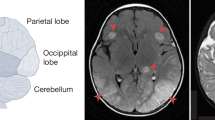

Extended Data Fig. 5 Immunohistochemical staining of HSV-1-infected brainstems.

a, Total RNA was isolated from microglia, neurons, and astrocytes obtained from newborn C57BL/6N mice, and analyzed for Tmeff1 mRNA levels relative to Bactin by RT-qPCR. Each dot represents one animal (n = 3). Two-tailed one-way ANOVA test for difference of means, followed by unpaired two-tailed t-tests of means of groups indicated by P-values. Error bars, ± s.d. P-values < 0.05 were considered statistically significant. b-c, Select examples of stainings visualized by fluorescence microscopy of brainstem sections from HSV-1-infected WT and Tmeff1−/− littermates (5 days p.i.) stained with DAPI, HSV-1 and, NeuN (neuron-marker) or DAPI, HSV-1, and S100 (astrocyte marker). Scale bar 10×, 50 μm; Scale bar 40×, 20 μm. Each brainstem (WT, n = 4 mice; Tmeff1−/−, n = 5 mice.) is represented by images of 3 different anatomic bregma (−5.80, −6.72, −7.20 mm) and images of left and right side HSV-1+ foci, pr. bregma site. d, Primary mouse microglia infected with HSV-1 (McKrea) at increasing MOI. Viral HSV-1 gB mRNA transcripts were evaluated by RT-qPCR and shown relative to Bactin, 24 h post infection. Each dot represents biologically independent samples (n = 3 pr genotype at different MOIs). e-g, Tmeff1−/− mice fully backcrossed for 10 generations to C57BL/6N background were infected in the cornea with HSV-1 (2 × 106 pfu/eye) and followed over time until reaching humane endpoint or recovering 100% of starting weight. e, % Weight change and f, Symptom scores. g, Survival curve (Uninfected, UI, n = 7; WT, n = 19, Tmeff1−/−, n = 17). Dead animals were censored in the graphs, and thus represented in the graphs with the weight and symptom score at the time of death. Survival was analyzed using a Log-Rank Mantel-Cox test, and a comparison of disease development (e + f, weight change and symptom score) between the groups were compared with a Mixed-Effect Analysis with Geisser-Greenhouse Correction for comparison of multiple interacting variables (time and genotype). Error bars; S.E.M., P-values < 0.05 were considered significant.